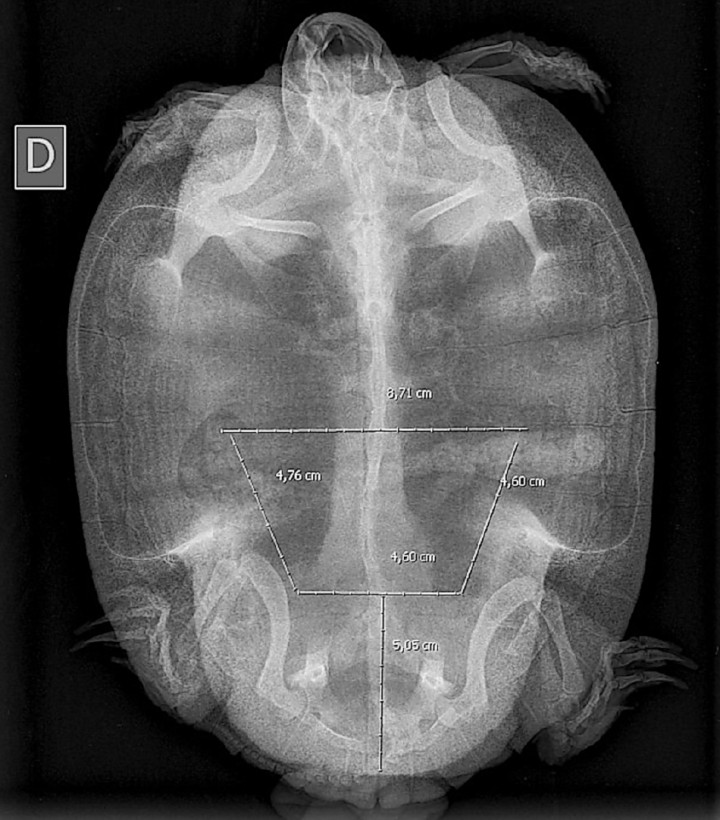

Se pautaron medidas de enriquecimiento ambiental para facilitar puestas futuras (instalar un receptáculo de fácil acceso con una mezcla de arena y turba) y, además, se ofreció la opción de esterilizar al animal como medida de supresión de la puesta una vez su recuperación fuera completa. Ocho meses después de la intervención, el propietario advirtió comportamiento de puesta pero ésta no llegó a efectuarse; tras realizar una radiografía y confirmar la presencia de huevos (Fig. 9) se instauró un tratamiento médico para inducir la puesta (Tabla 3[ Montesinos A, Ardiaca M: Guía terapéutica en animales exóticos. Barcelona, Multimédica ediciones veterinarias, 2017; 17, 54, 179. , Carpenter J, Klaphake E, Gibbons P, Sladky K: Reptile formulary. En Mader´s Reptile and Amphibian Medicine and Surgery (third ed), St Louis, Saunders Elsevier, 2019; 1192-1193, 1198, 1200, 1205-1206. ]), que resultó exitoso a las pocas horas.

Radiografía dorsoventral a los 8 meses de la cirugía con presencia de estructuras ovoides con radiodensidad mineral compatibles con huevos.